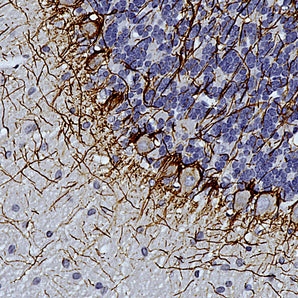

Mouse Monoclonal Antibodies